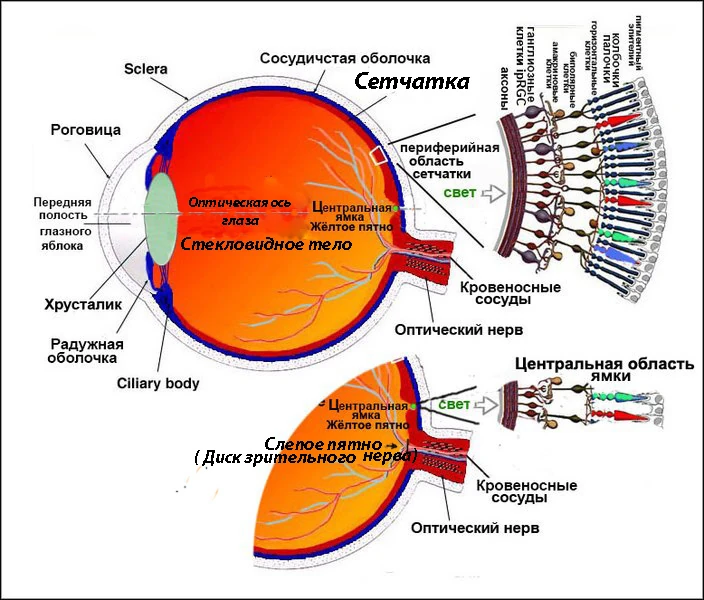

Изображения и анатомия сетчатки глаза

Раздел: Визуальный дайджест